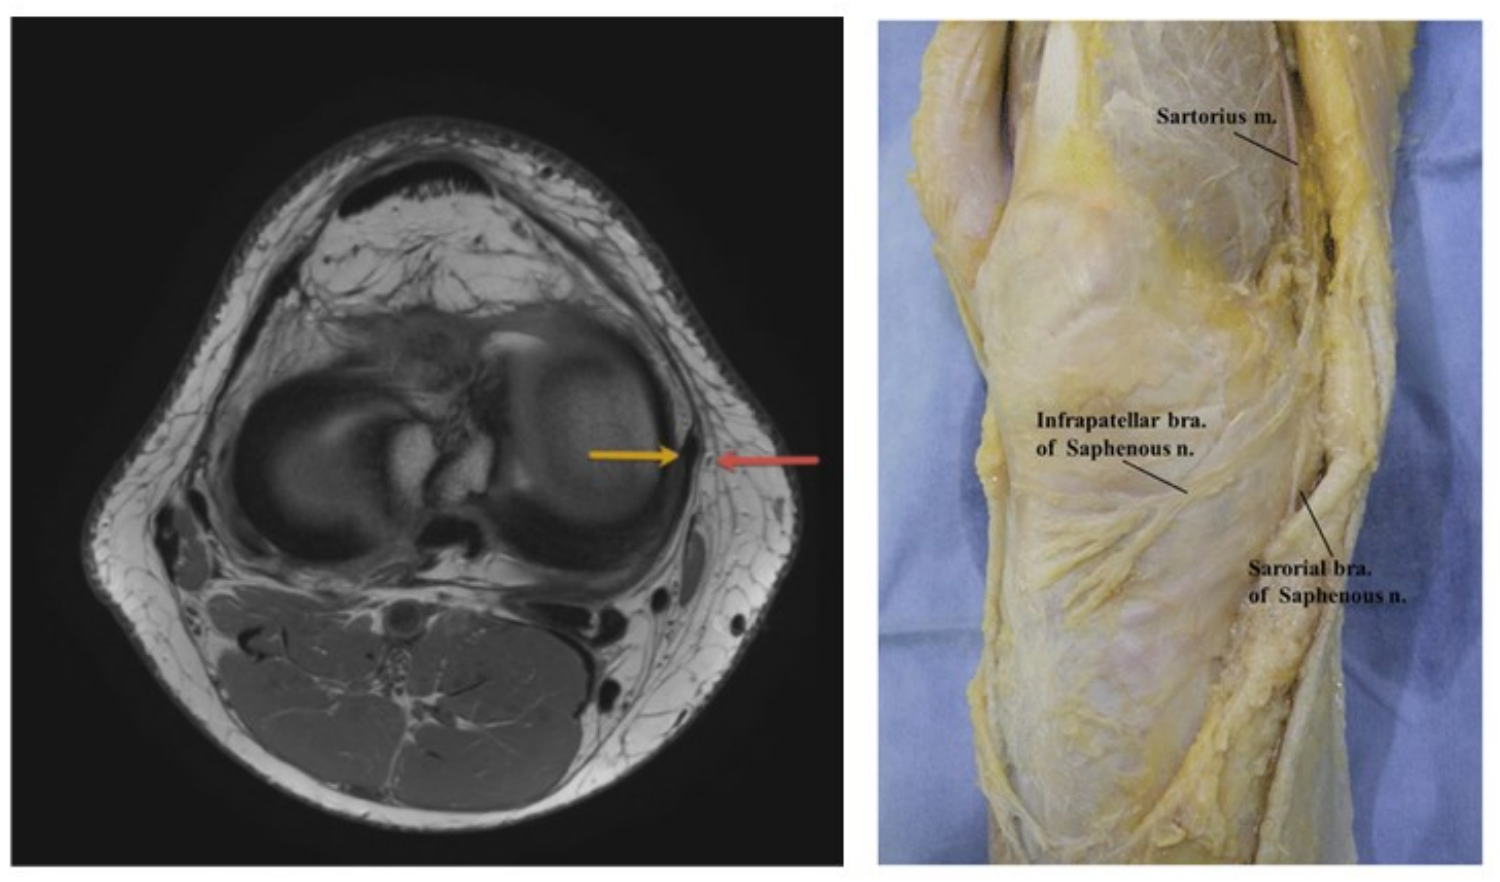

Криоанальгезия коленного сустава:

infrapatellar branch of the saphenous nerve

infrapatellar branch of the saphenous nerve (IBSN) and anterior femoral cutaneous nerve (AFCN)